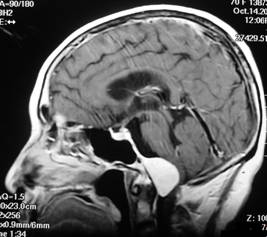

5.CT和MRI掃描 可確定腫瘤的部位和大小,絕大多數可作出定性診斷。CT掃描示邊界清晰的均勻高密度影,增強後顯著。少數呈混合密度或低密度改變。MRI見腫瘤多數呈等信號,增強後明顯強化。

根據病史、臨床表現,結合CT及MRI影像檢查,一般可以得到確診。

20世紀70年代診斷主要依靠脊髓碘油和腦室碘油造影。造影片顯示枕骨大孔區邊界清晰的充盈缺損。近年國外多以甲泛影葡胺脊髓造影CT掃描,代替繁瑣的傳統脊髓造影及腦室碘油造影,經對比CT掃描,3/4的病例得以確診MRI是診斷顱後窩和上頸段腫瘤的最佳方法,經增強MRI掃描幾乎100%枕大孔區腫瘤可以得確診。